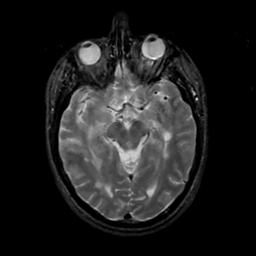

MR Study #12, May 12, 1991 -- Slice #21